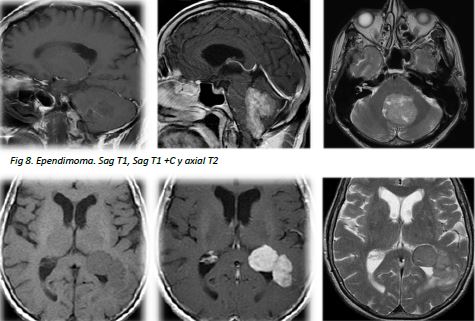

• Hallazgos típicos de imagen mediante TC y RM con puntos clave que orientan su diagnóstico